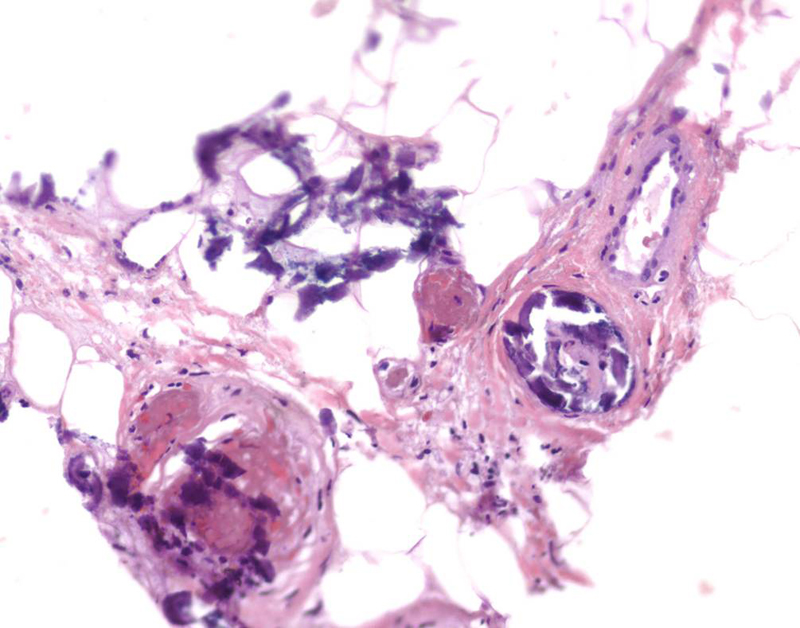

From www.dreamstime.com

Histology of Abnormal Tissue (calcium) Stock Photo Image of Calcium Deposits From Dialysis Calcium balance in haemodialysis patients. Many people who get calciphylaxis also have kidney failure or receive dialysis. Predialysis oxalate levels of 50 to 70 μmol/l should be targeted with aggressive dialysis: In patients receiving intermittent haemodialysis treatment, calcium balance. It's not known why people with kidney failure or people receiving dialysis are at higher risk of. In the 1960s, calciphylaxis. Calcium Deposits From Dialysis.